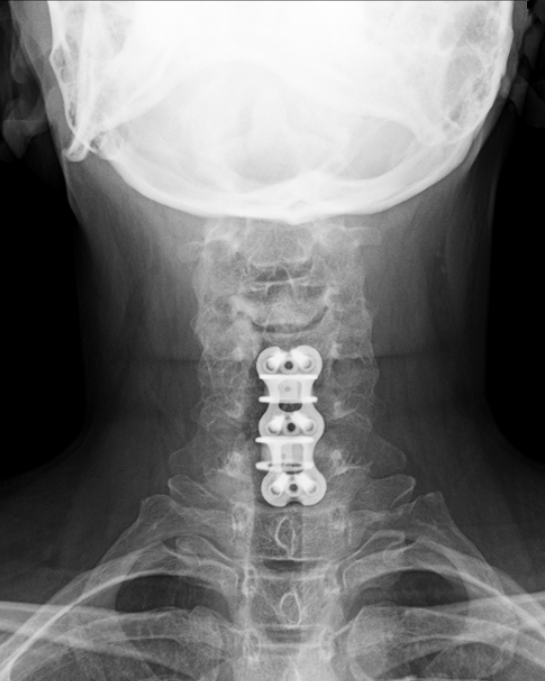

10 years ago today I had my first spinal surgery (yes, first…more on that in a minute…) To say it changed my life would be the understatement of the decade. I went from a daily headstand practice to barely being able to lift a glass of water practically overnight. The kicker is that I was “really healthy” (thin, vegetarian, and TEACHING yoga) and “nothing happened” to me. There was no accident or injury; just a lot of stress and crappy discs. Before I knew it, I was waking up from surgery with 2 replacement cages & a plate fusing 3 vertebrae.

- I think my x-rays are really cool and wanted to share them!

I hope you’ve enjoyed this little tour of my spine (cross your fingers this is the last intervention!) and as always, if I can be of service to you, please do not hesitate to reach out to schedule a Complimentary Design Discovery Consultation.